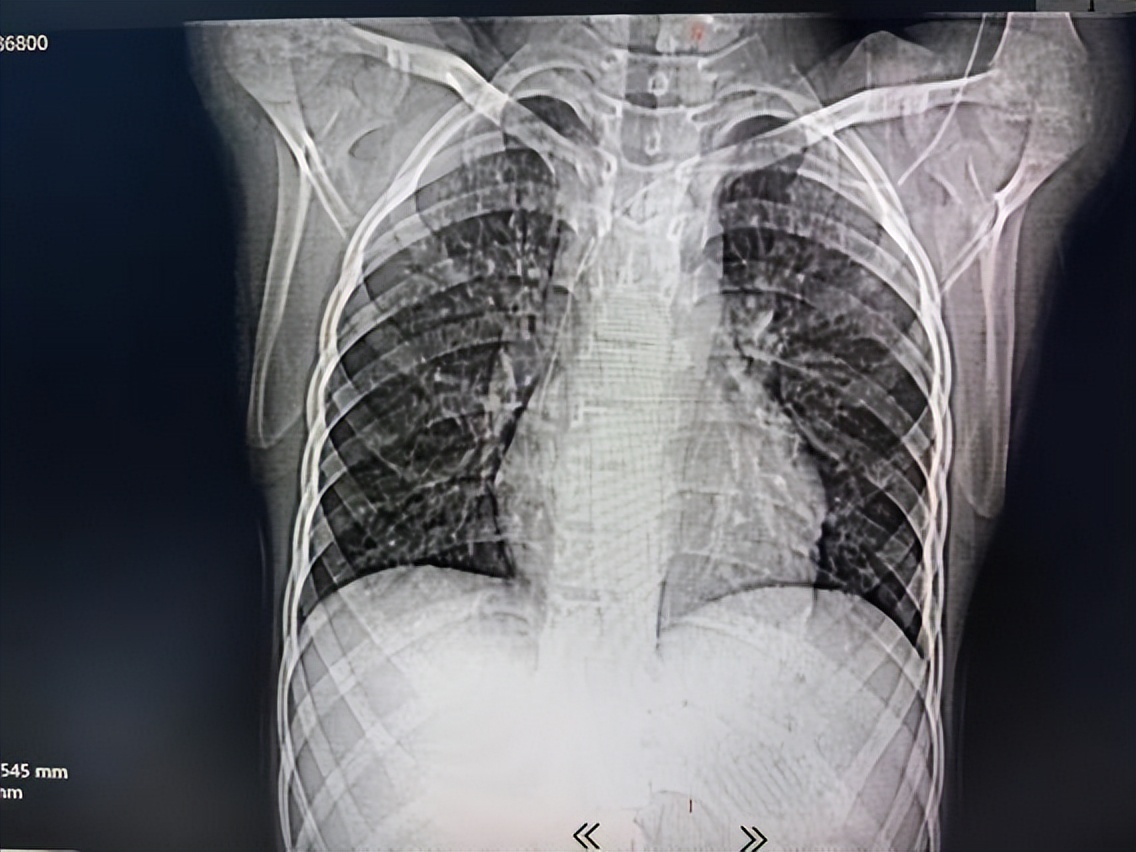

术前CT及胸片显示腋静脉段导管(箭头示)弯折断裂。

随后复查CT及三维重建显示:导管断裂,远端漂移至右下肺动脉。